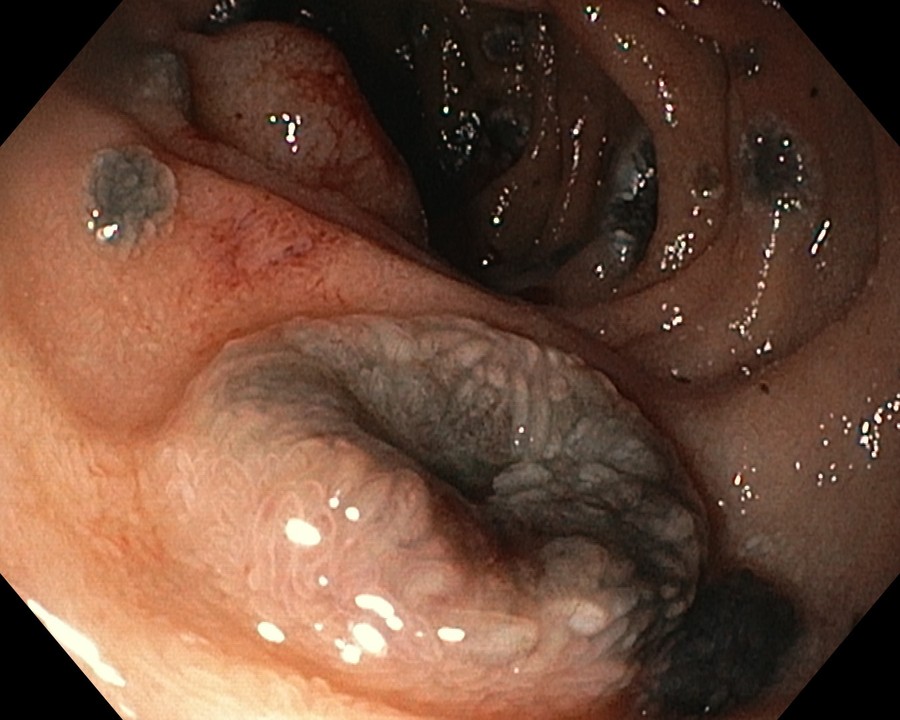

- Атлас